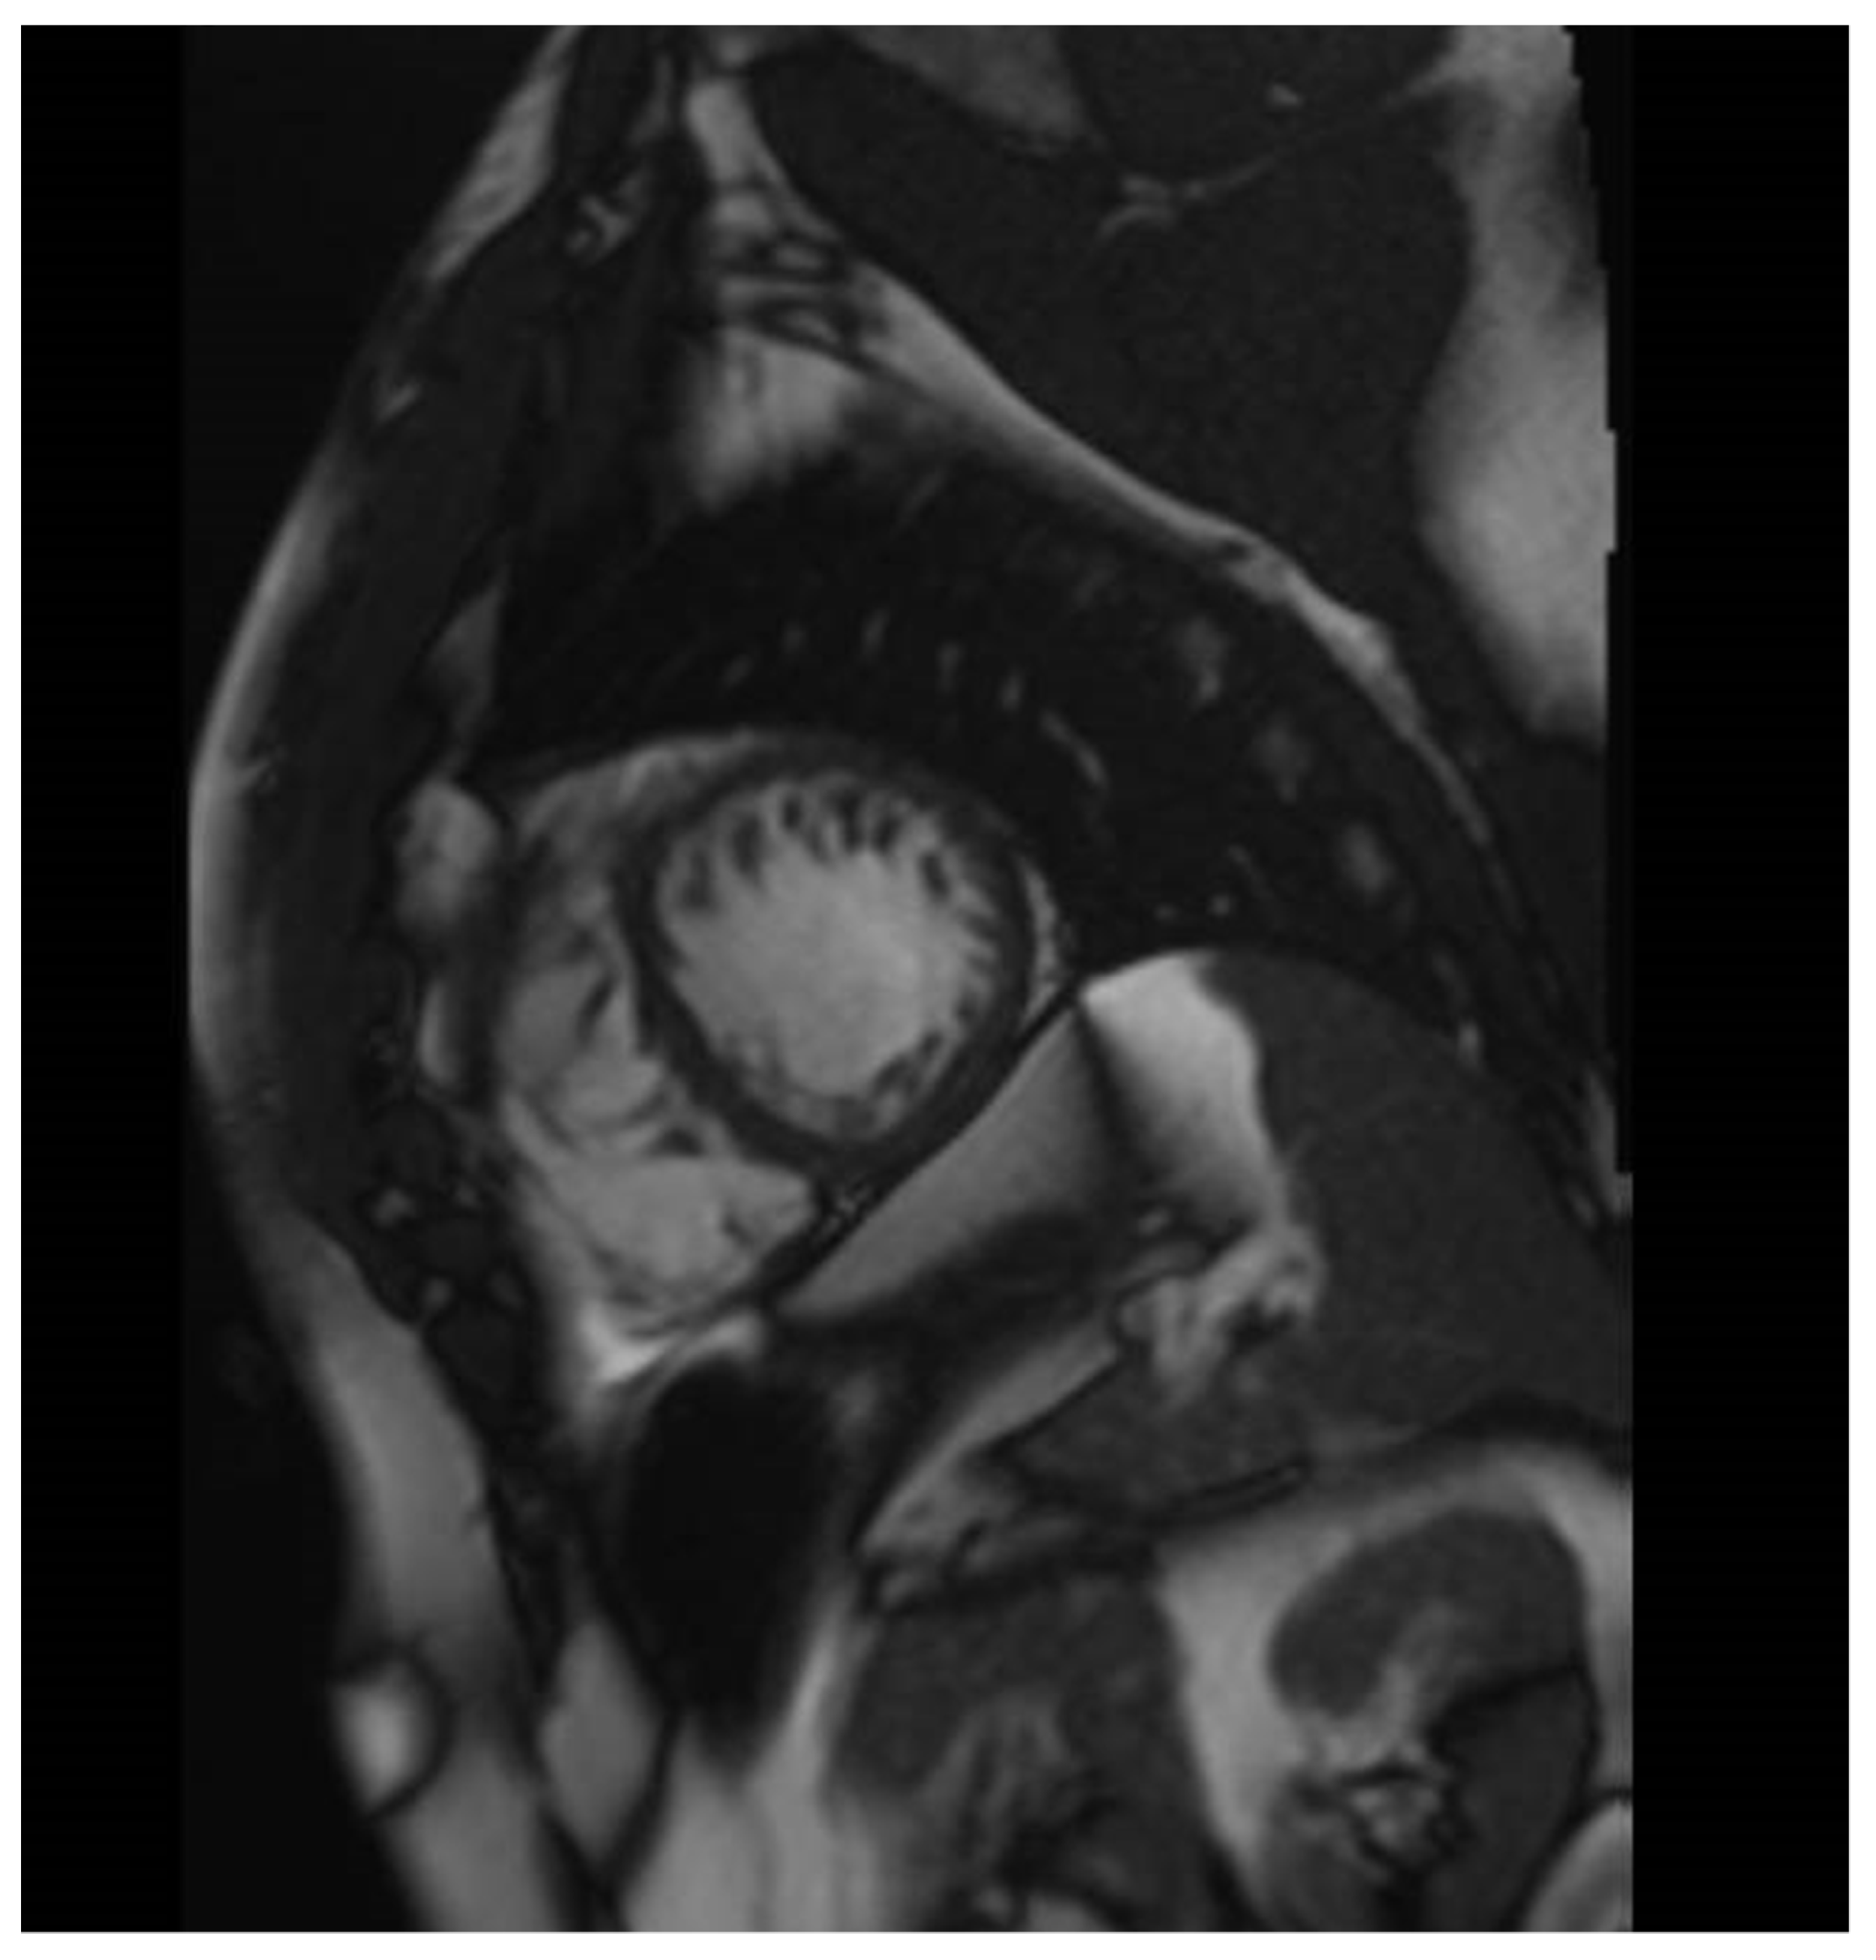

2. The Case